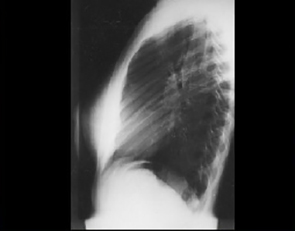

PA and Lateral

Click on the xrays to enlarge them.

Choose the best interpretation of the chest X rays:

Normal

Normal heart & lungs

with straightened spine

Normal heart & lungs with scoliosis

with pectus excavatum

Normal heart & lungs with kyphosis